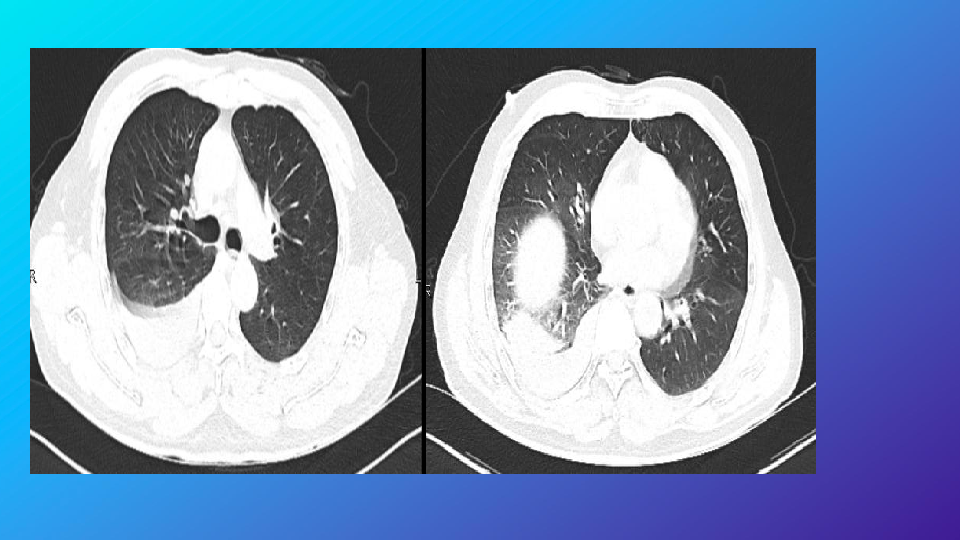

胸部外伤